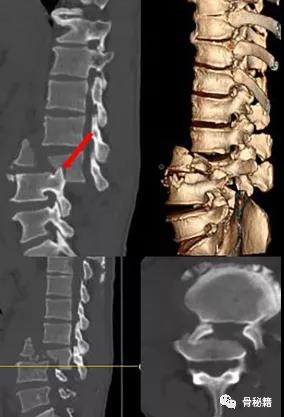

前后移位

对于前后移位就相对复杂一些1、解锁脊柱的关节面

如果坎墩严重,需要先植入椎弓根螺钉,咬除部分后方椎板,进行后柱的撑开。